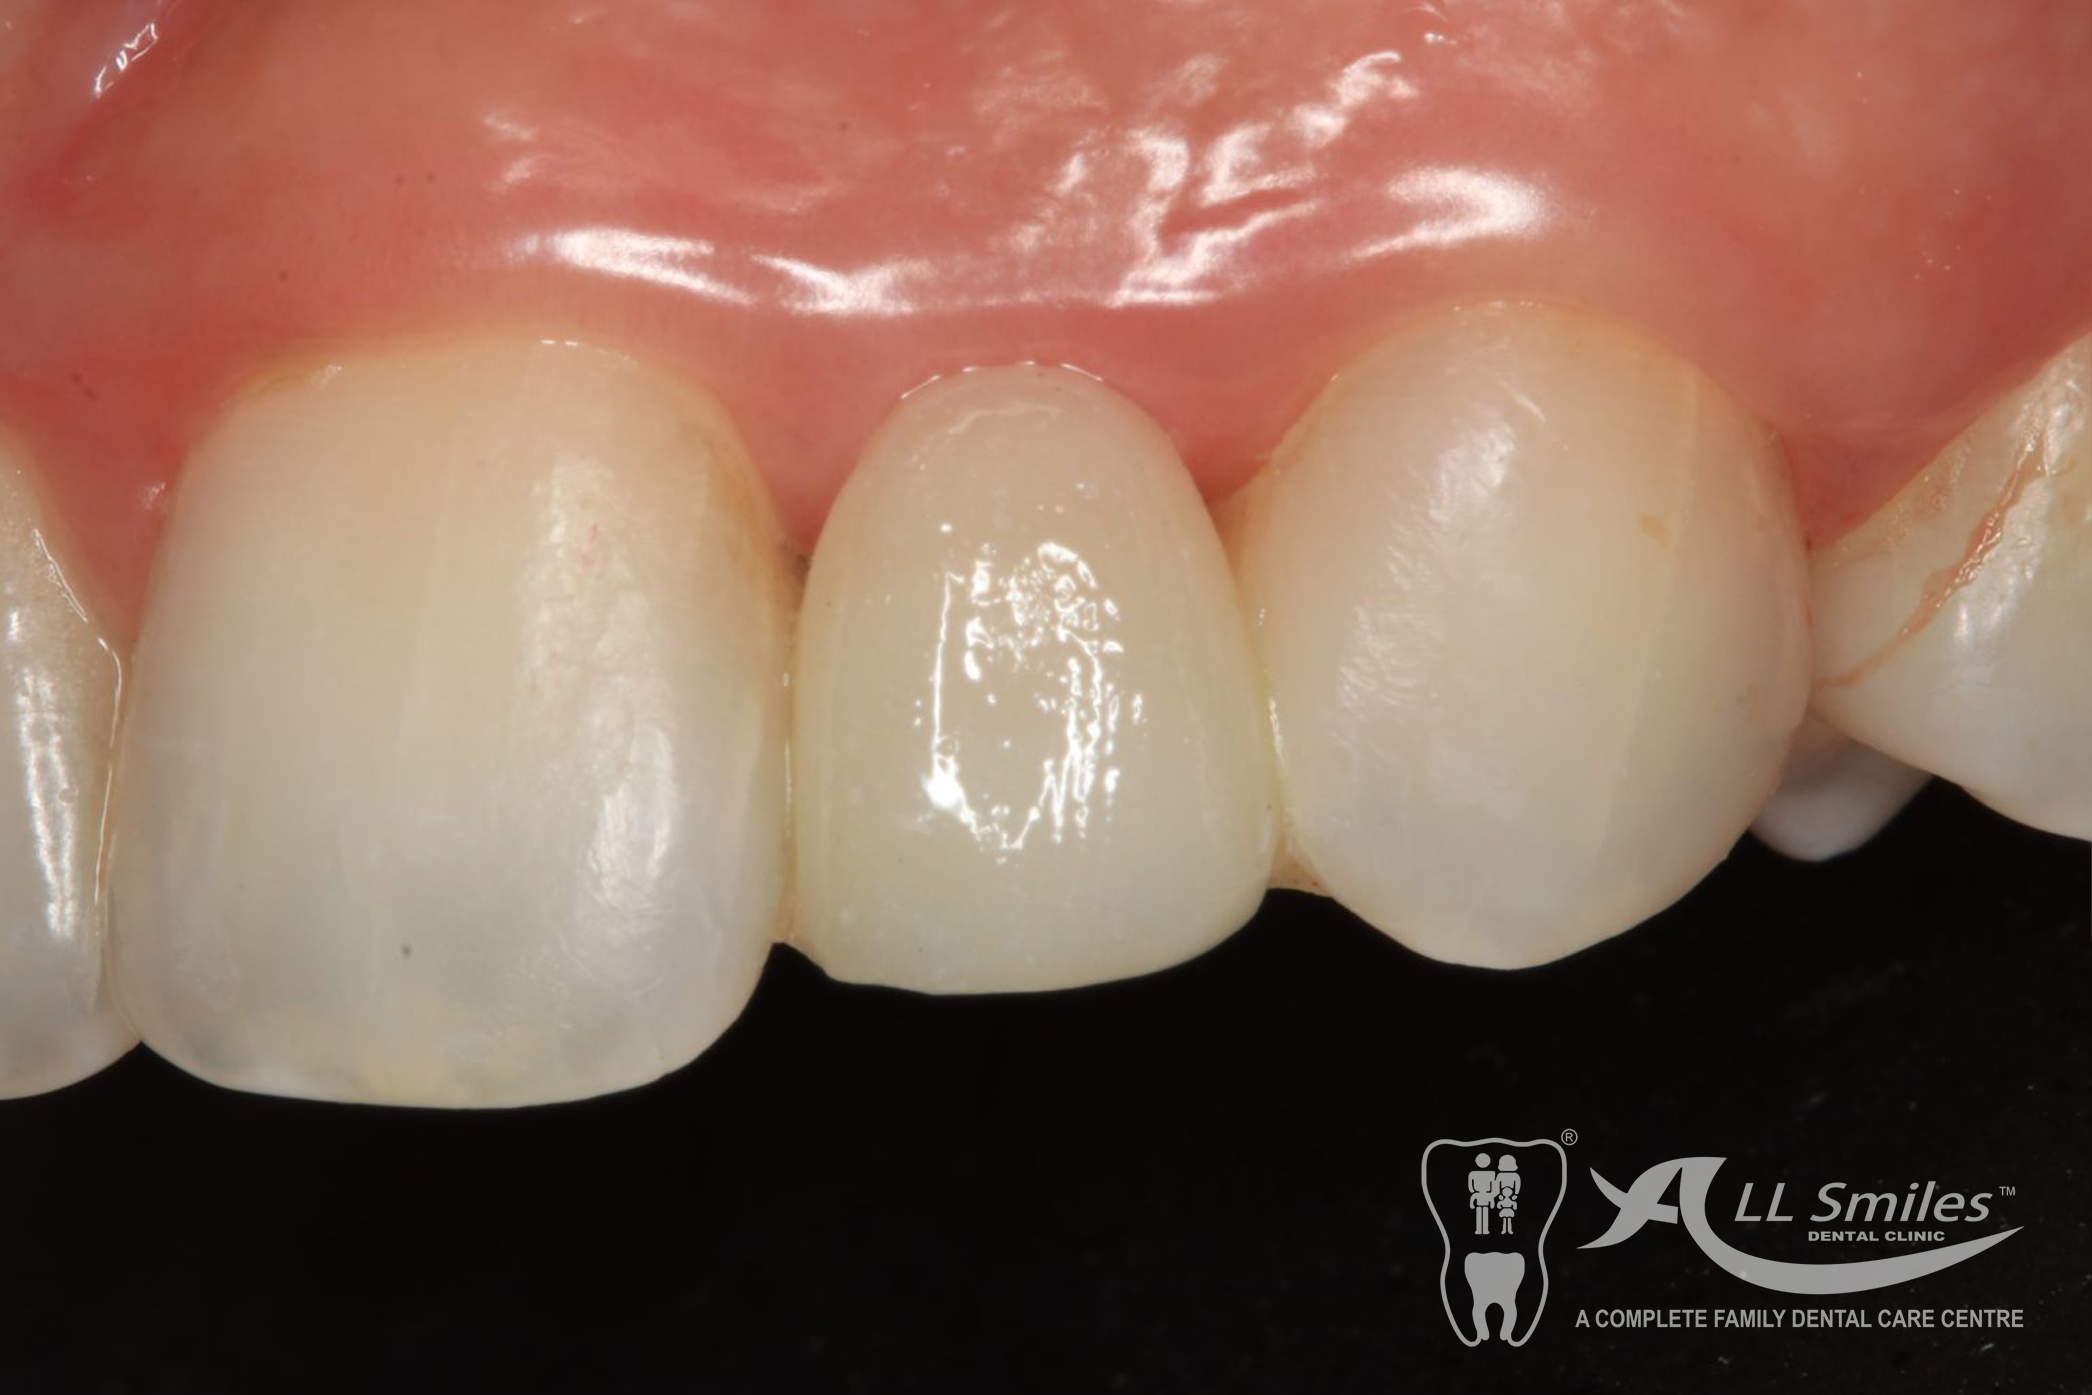

Crowns & Bridges Gallery